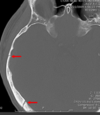

Which dural fold is the arrow pointing to

Tentorium cerebelli

Tentorial notch

Falx cerebelli

A